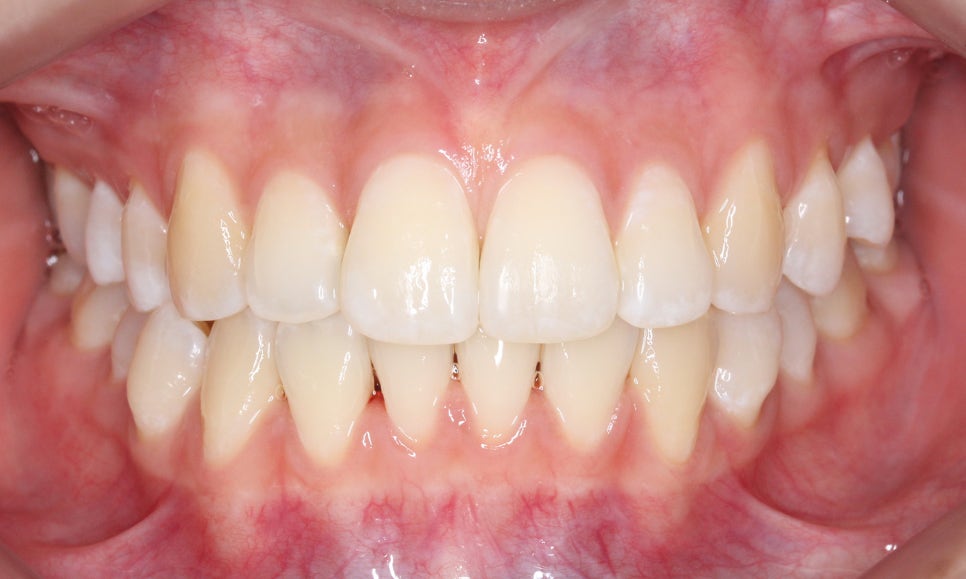

클리피씨교정 전

2D치과

신논현치과 자가결찰브라켓 Case의

교정 전 치아 상태입니다.

정면에서 본 치아의 전체적인 모습을 보면

상대적으로 구치부보다 전치부의 치열이

삐뚤어져 있는 상태로 12번(측절치)의

반대교합이 눈에 띄는 모습입니다.

치아 개방 시 상악과 하악의 정중선을 보면

대각선으로 삐뚤어져 있는 것을 확인할 수 있는데요,

안모의 중심이 틀어져 있기 때문에 치아 개방-교합 시

한쪽으로 힘이 가중될 가능성이 있습니다.